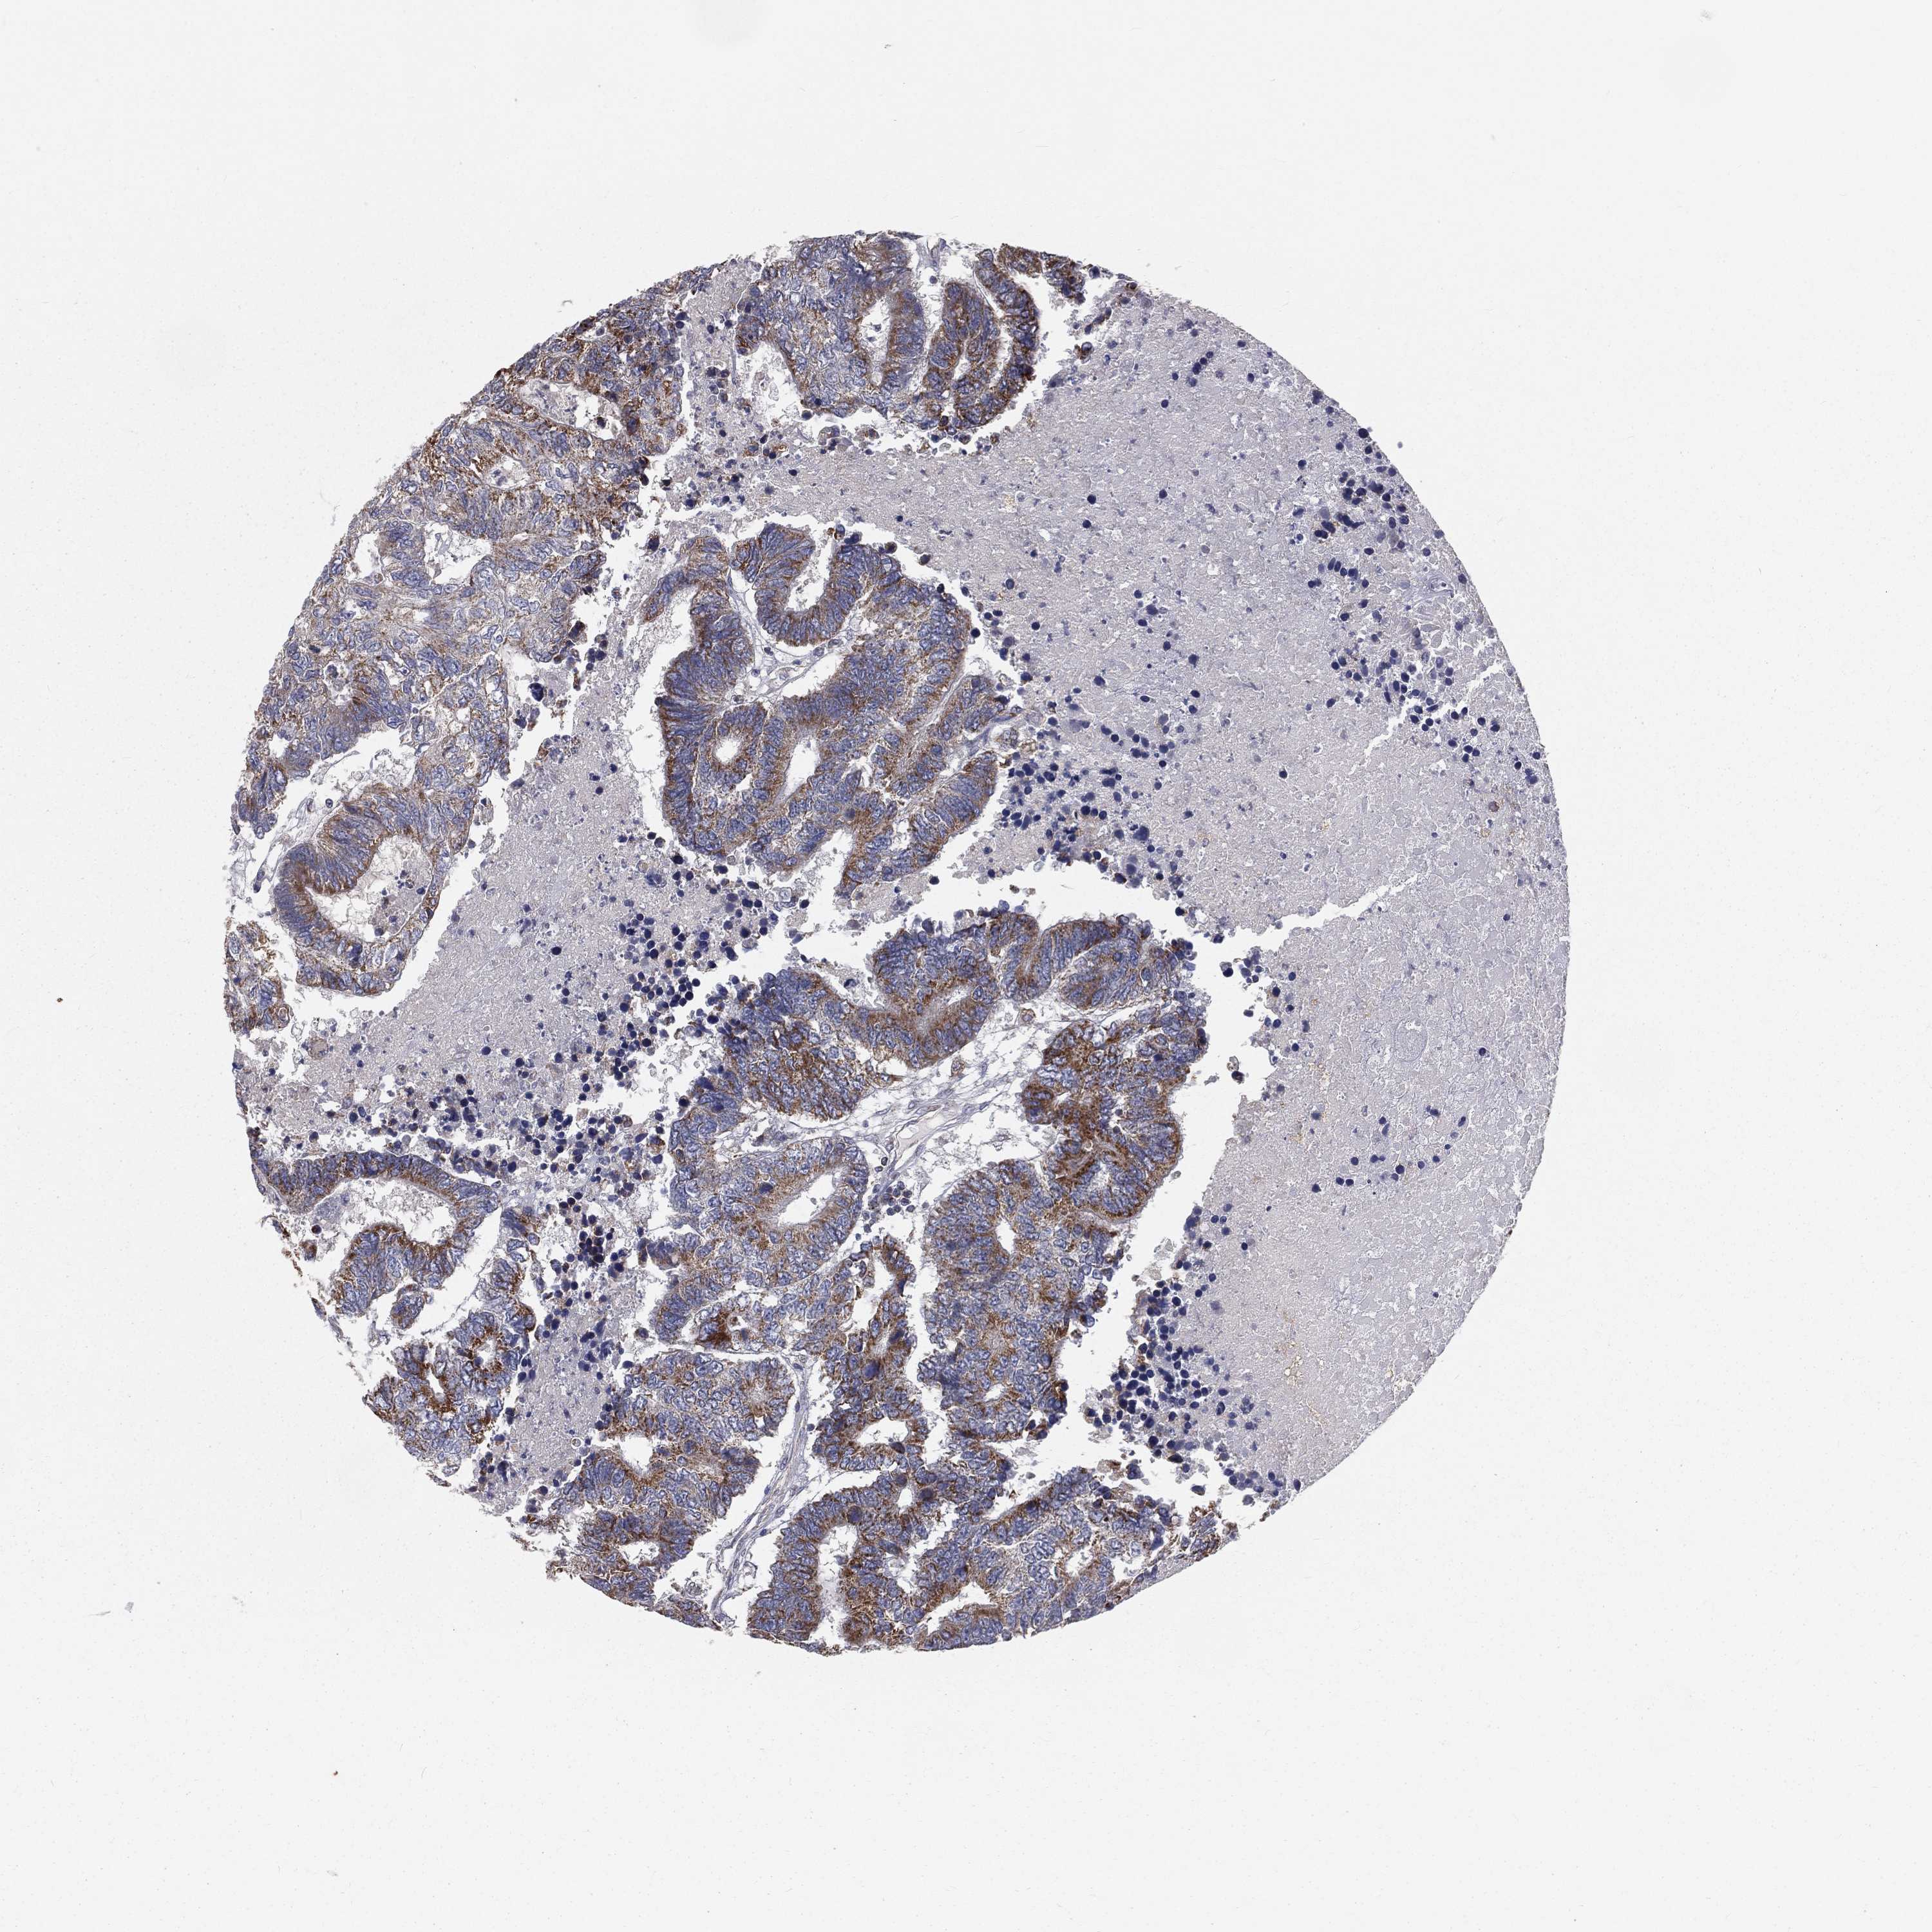

CANCER COLORECTAL CANCER Show tissue menu

Colorectal cancer

Human cancer

Colon adenocarcinoma